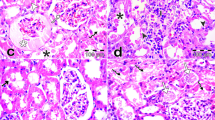

The control group exhibited normal renal glomerular and tubular structure in the cortical and medullary areas. The gentamicin group exhibited pathological abnormalities in the glomerular and tubular structures. Specifically, there was degeneration of the glomerular wall and some hypertrophy, as well as mononuclear cell infiltration, tubular epithelial cell degeneration, and inter-tubular hemorrhage (Fig. 3). The cisplatin group exhibited severe glomerular congestion, with infiltration of the inflammatory cells within the interstitium and severe hemorrhaging in the medullary and cortical areas. Furthermore, severe necrosis was observe in the tubule (Fig. 3).

A Control (renal tubules are normal) B. Gentamycin group C cisplatin group. Many cortical convoluted tubules were revisited by necrotic epithelial cells (horizontal solid arrows) or vacuolated swell cells (arrow heads), glomeruli exhibited swelling with reduction of bowman’s capsular space. Shown are numerous inflammatory cells (small hollow vertical arrow) in the glomerular and tubular structures in the outer medulla